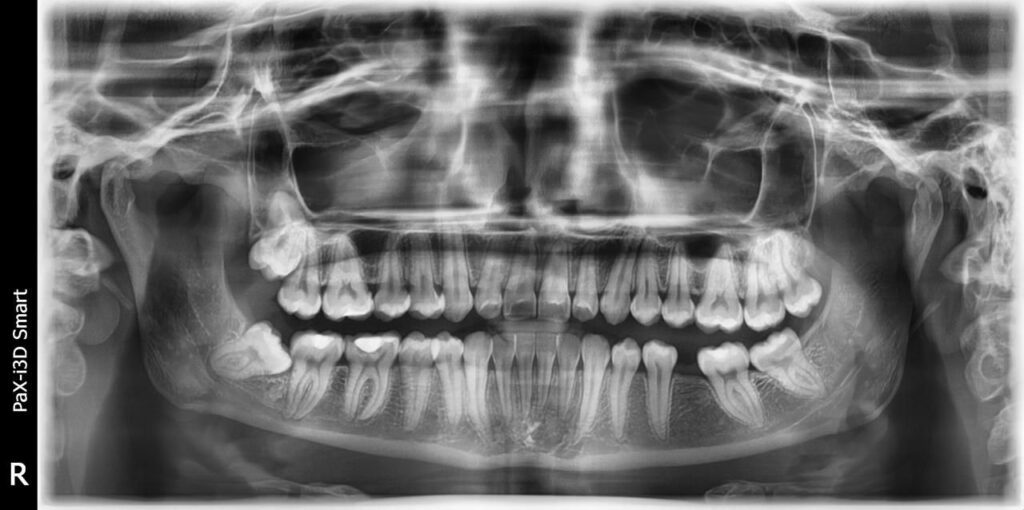

Raio-x Panorâmico e teleradiografia

Panorâmico

fornece visão de toda a arcada dentária para avaliação geral da saúde bucal.

Telerradiografia lateral analisa o perfil ósseo facial e o posicionamento dos dentes, auxiliando no diagnóstico e planejamento ortodôntico